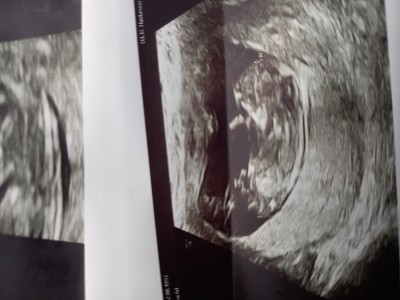

tepki gösterecek olanlar lütfen yazmasın kız erkek tabi ki farketmez ama anneyiz sonuçta insan merak ediyo aslında apaçık ama doktor erken diye söylemek istemedi galiba

Kız bebek gibi cknti aşağıda

Çıkıntı aradım bnde ama göremedim açıkçası çıkıntı dediğiniz ayağı degilmi

Kaç haftalık usgdeki

12+1 canım